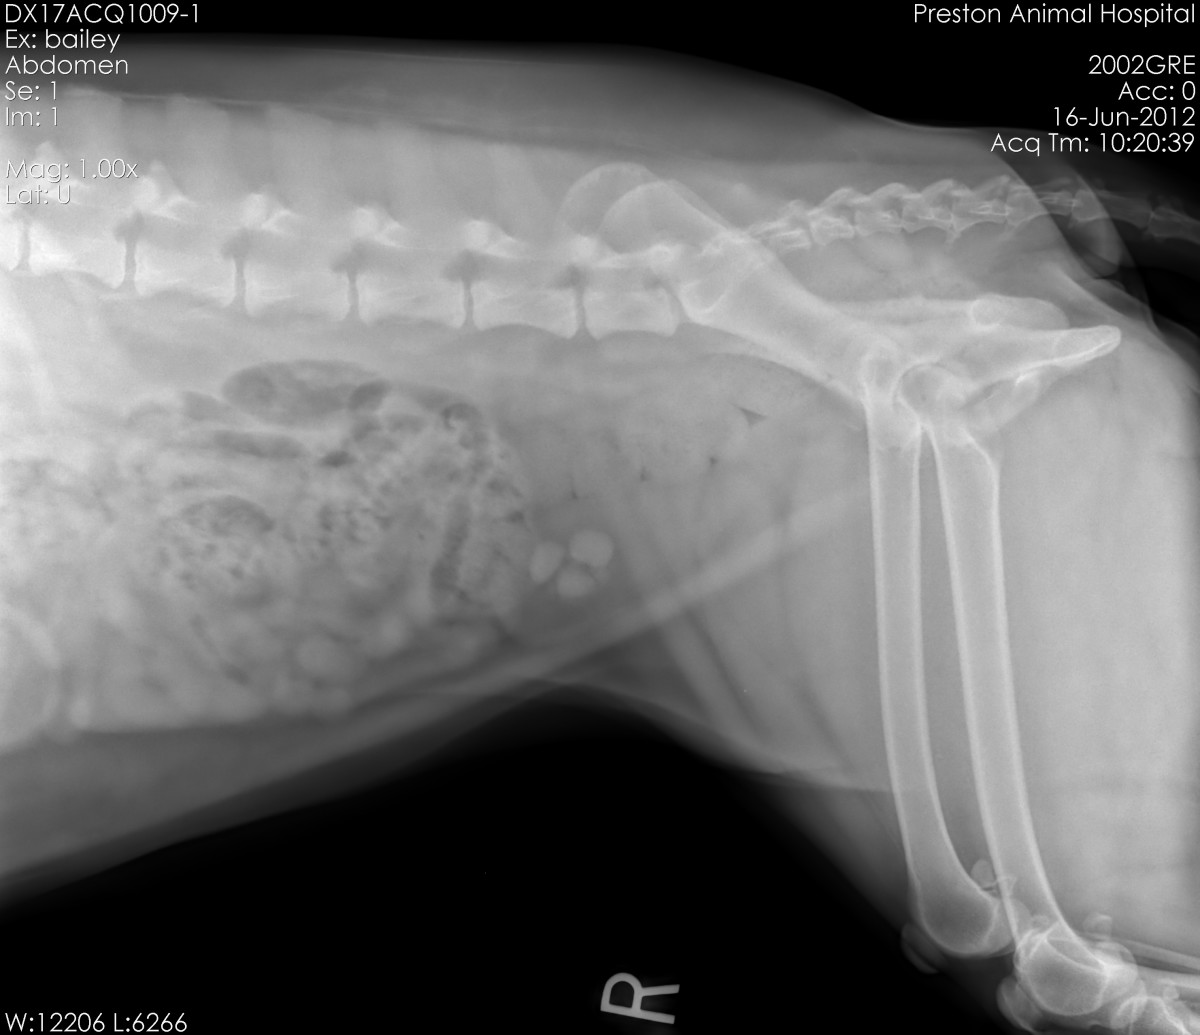

From buyxraysonline.com

BLADDER STONEDOG Dog Treatment Bladder Stone There are three main treatment options for bladder stones: Nephrolith = kidney stone, ureterolith = stone within ureter, cystolith or cystic calculus = bladder stone, urethrolith = stone within urethra. When symptoms are at their most intense, this is often a sign of a larger stone which may. Learn about bladder stones in dogs, including common types of stones (struvite. Dog Treatment Bladder Stone.